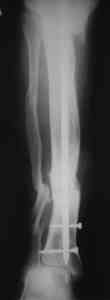

Пример (пациент 46 лет, лечился у нас 4 года назад, внутренний остеосинтез выполнен с определенными погрешностями, но перелом сросся и рецидива инфекции не было): рис. 1,2 - при переводе к нам в институт, рис. 3 - после микрохирругической пластики, рис. 4, 5 - после интрамедуллярного остеосинтеза, рис. 6, 7, 8 - внешний вид и рентгенограммы после окончания лечения

Больному была выполнена операция. после демонтажа аппарата Илизарова столкнулись с "прямо на глазах" сокращением регенерата. Гвоздь сквозь регенерат удалось провести без технических трудностей. Сложности были с репозицией отломков, что связано с выраженным остеопорозом, их короткими размерами. Пришлось применить полер-винт. Выполнили блокирование. По причине укорочения регенерата пришлось повторно смонтировать аппарат Илизарова и начать транспорт фрагмента на гвозде (14 мм). Больному разрешена ходьба с дозированной нагрузкой на больную ногу. Контрольные рентгенограммы прилагаются. Нынешняя ситуация породила ряд вопросов и замечаний: